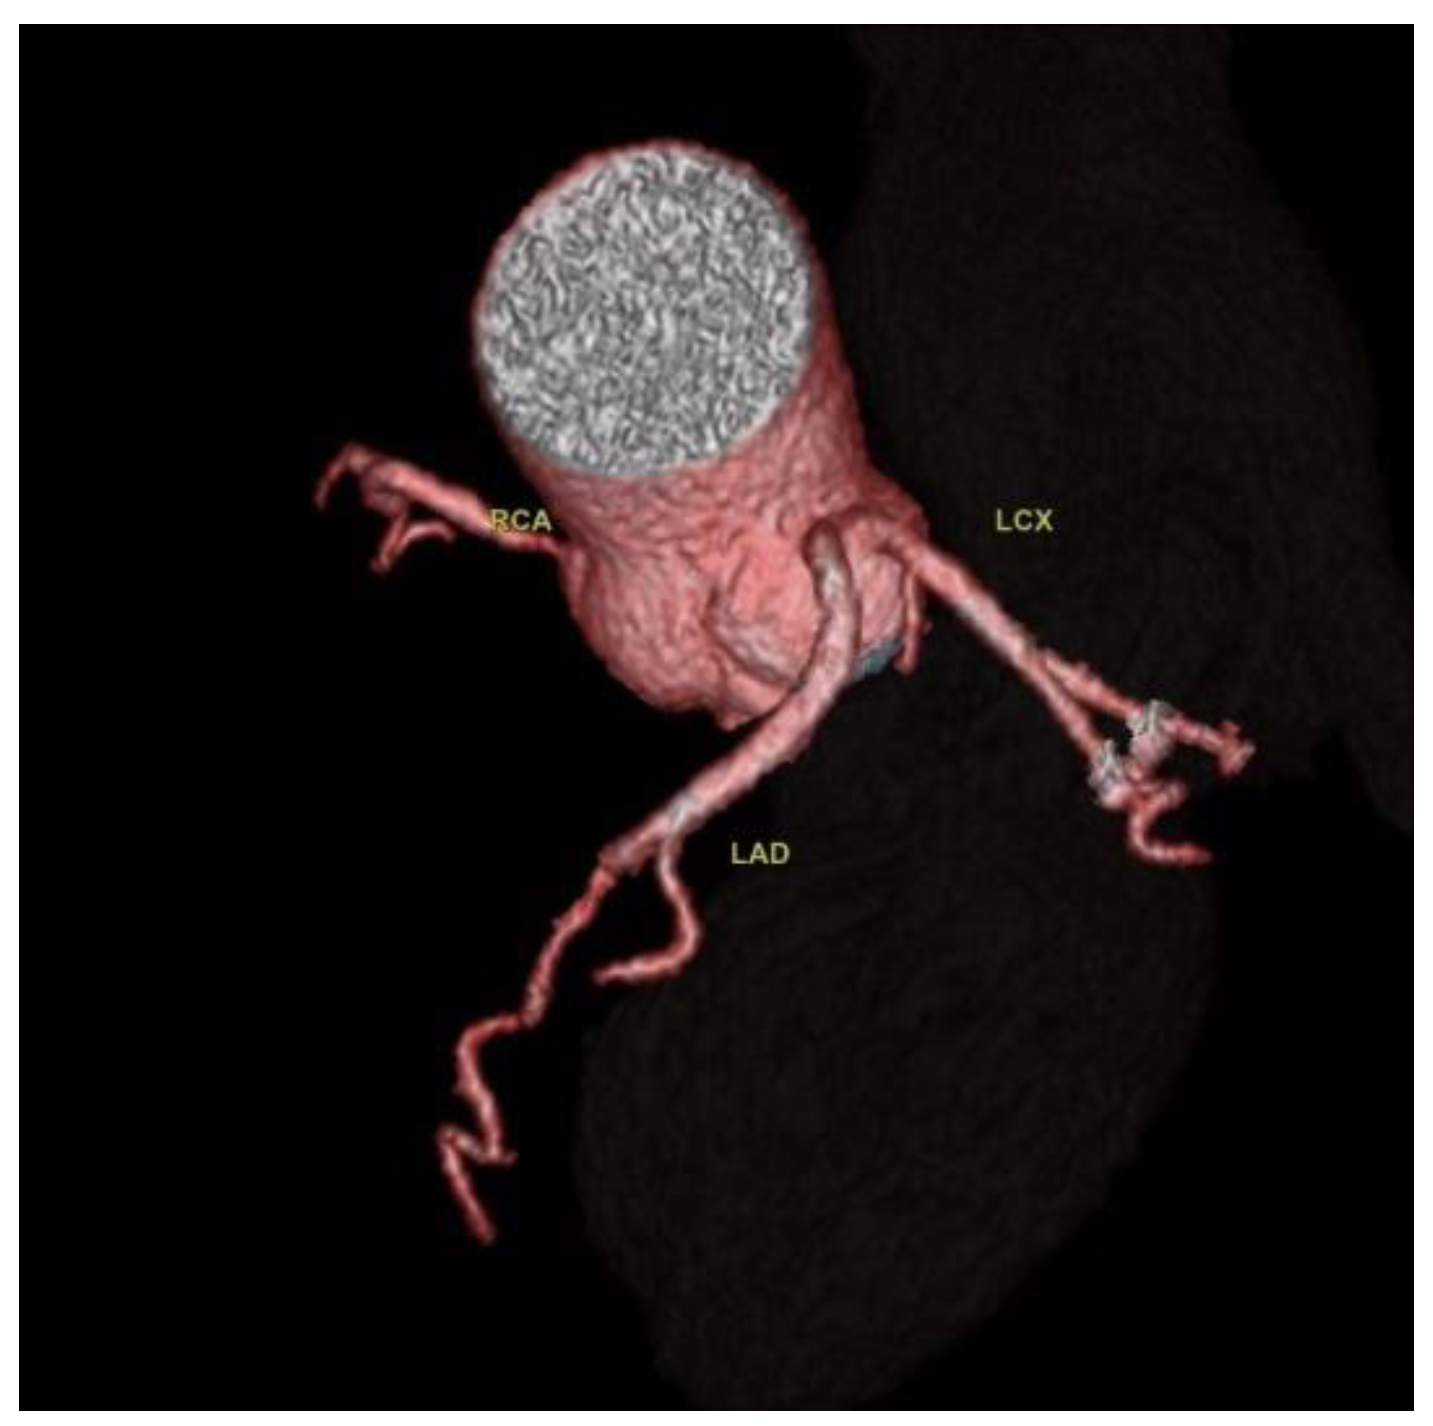

Two cases of separate origins of LAD and LCX arising directly from the left coronary sinus were found, as illustrated in

Figure 3.

Two cases of separate origins of the LAD and LCX directly from the left coronary sinus were detected. Separate origins of LAD and LCX from the left coronary sinus is considered a benign variant, but some CAA classifications include it. It is considered a common CAA with a frequency between 0.41% and 0.67% [

5,

24].